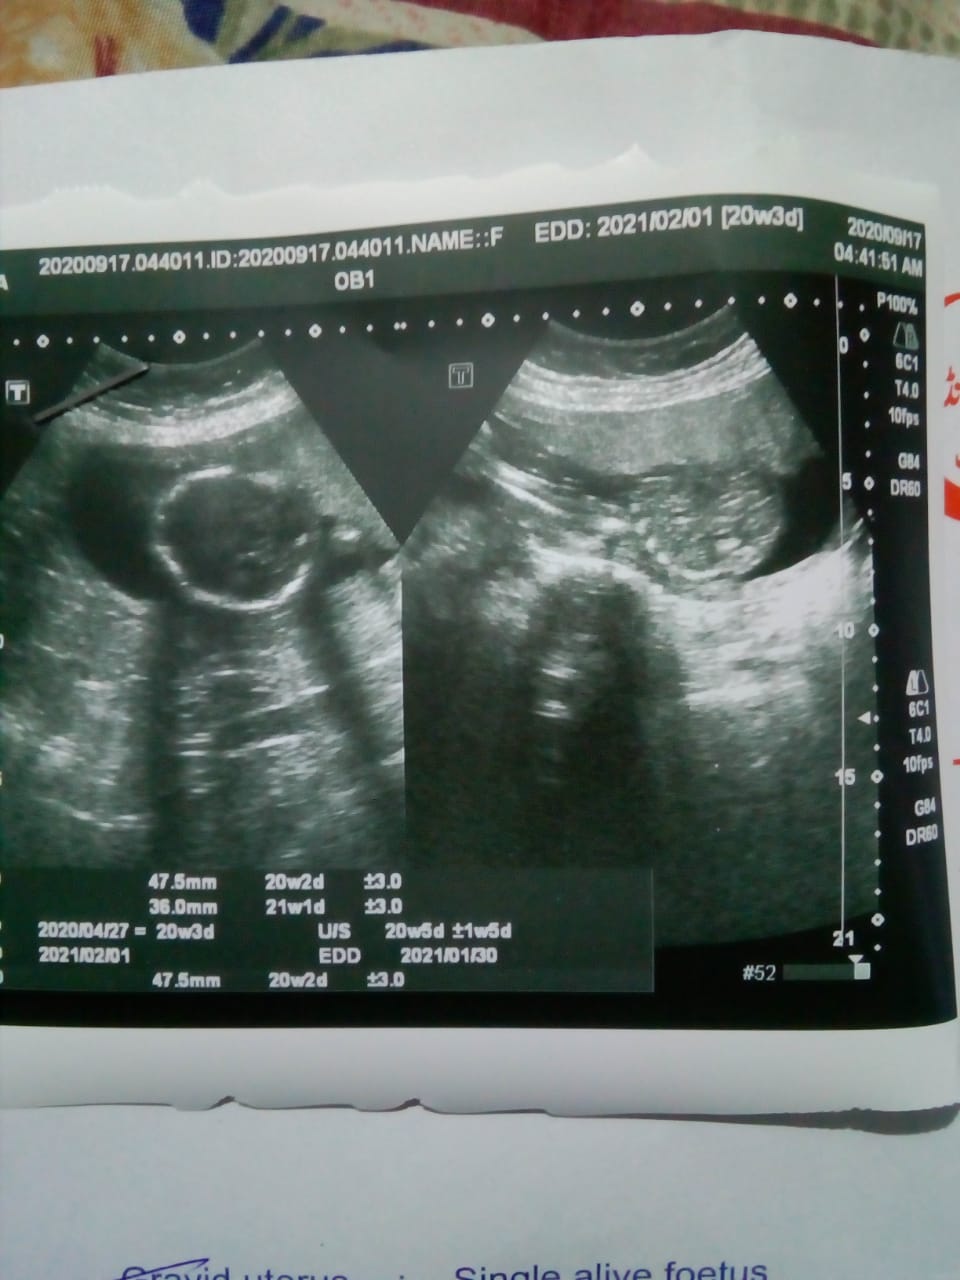

Please guess the gender of my baby 20w 3 days old. I already have three girls.

Do you have other pictures? In these pics, it's just of baby's head.

In the right picture it's hard to tell but it looks like just part of baby's spine. There's no genitalia in any of these pictures.